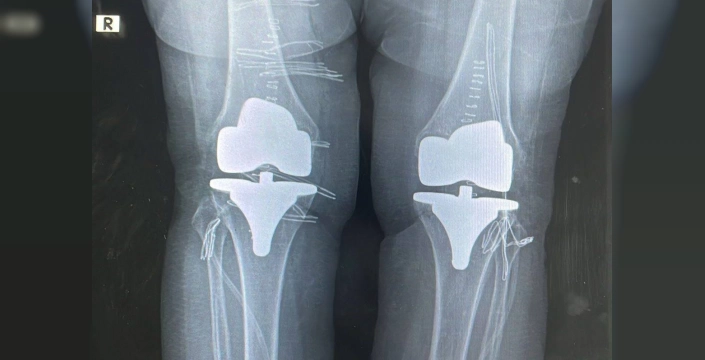

Bayburt Devlet Hastanesinde, Op. Dr. Reşat Arıkan tarafından 73 yaşındaki bir hastaya çift taraflı total diz protezi ameliyatı yapıldı. Başarılı geçen ameliyatla hastanın diz ağrıları giderildi ve sağlık durumu iyi.

Bayburt Devlet Hastanesinde gerçekleştirilen bir operasyonla, 73 yaşındaki bir hastanın dizlerindeki şiddetli ağrılar giderildi. Ortopedi polikliniğine başvuran hasta, ileri derecede kireçlenme teşhisi konulmuştu.

Ortopedi ve Travmatoloji Uzmanı Op. Dr. Reşat Arıkan tarafından yapılan ameliyat, çift taraflı total diz protezi uygulamasını içeriyordu. Ameliyat başarılı bir şekilde tamamlandı ve hastanın sağlığına kavuştuğu belirtildi.

Tek seferde yapılan bilateral ameliyatın ardından hastanın sağlık durumunun iyi olduğu hastane yetkilileri tarafından açıklandı. Hastanın dizlerindeki ağrılarının giderilmesiyle yaşam kalitesinin artması bekleniyor.